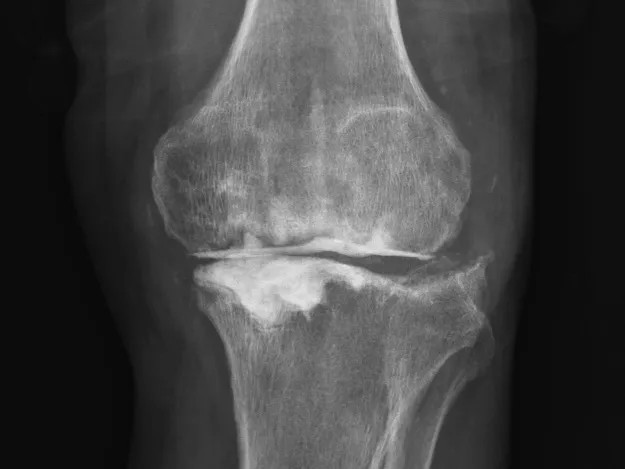

68歲的張先生(化名),本以為一次膝關(guān)節(jié)單髁置換手術(shù)能終結(jié)他的疼痛。然而,術(shù)后感染不期而至,將他的生活拖入長(zhǎng)達(dá)8個(gè)月的灰暗期。

膝關(guān)節(jié)持續(xù)紅腫、疼痛,每一步都伴隨著不適與恐懼。反復(fù)治療,效果卻不盡如人意。傳統(tǒng)手段面對(duì)此類術(shù)后感染、結(jié)構(gòu)遭破壞的復(fù)雜局面,往往力不從心,患者可能需要經(jīng)歷多次手術(shù),且功能恢復(fù)難以保障。

清創(chuàng)只是第一步,如何在一片“復(fù)雜地形”中重建一個(gè)穩(wěn)定、功能良好的膝關(guān)節(jié),是更大的挑戰(zhàn)。為此,團(tuán)隊(duì)引入了計(jì)算機(jī)輔助手術(shù)規(guī)劃系統(tǒng)。

通過(guò)患者的CT數(shù)據(jù),系統(tǒng)構(gòu)建出膝關(guān)節(jié)的三維數(shù)字模型,精確評(píng)估骨缺損的范圍與形態(tài)。醫(yī)生可以在虛擬空間中,提前模擬手術(shù)過(guò)程,為患者“量體裁衣”,規(guī)劃出假體安放的最佳位置、角度以及所需填充骨缺損的特殊墊塊型號(hào)。